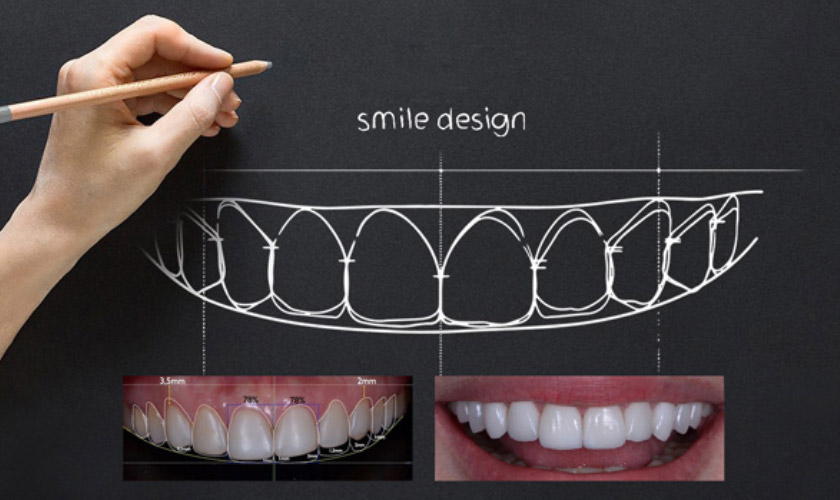

Smile Design – Công nghệ thiết kế nụ cười hoàn hảo

Thiết kế nụ cười là quá trình cải thiện nụ cười với sự trợ giúp của máy tính thông qua phần mềm chẩn đoán, phân tích và lập kế hoạch điều chỉnh thẩm mỹ cho nụ cười (Smile Design Software). Các Bác sĩ sẽ xem xét toàn diện sự hài hòa về hình dạng, màu sắc của răng với nướu, môi, da và toàn bộ khuôn mặt của khách hàng, kết hợp với các thủ thuật nha khoa khác như: điều chỉnh nướu, ghép nướu, sứ veneer, implant nha khoa, tẩy trắng răng, chỉnh nha,… nhằm khắc phục các khiếm khuyết và đem lại nụ cười đẹp rạng ngời cho khách hàng.

Phân tích màu sắc, tỉ lệ chuẩn giữa môi, nướu và răng